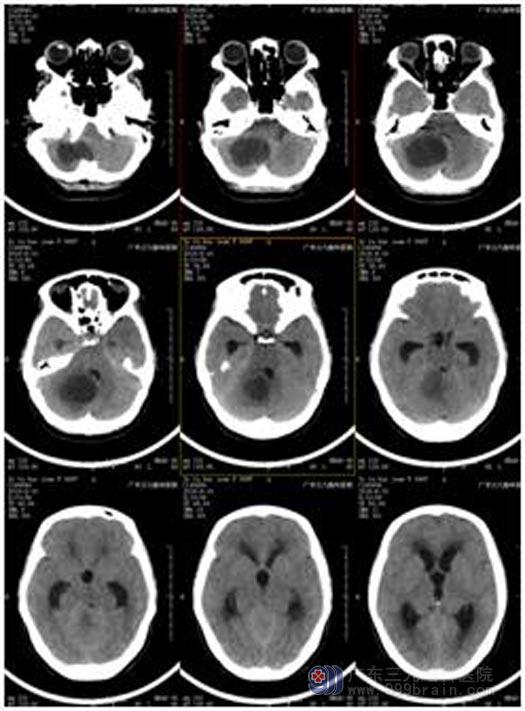

为找出原因,家人带着惠姨来到广东三九脑科医院综合神经外科。CT检查结果显示:右侧小脑半球存在5.5cm×3.6cm×3.0占位性病变,小脑扁桃体下疝形成,幕上梗阻性脑积水,初步诊断1.右侧小脑半球囊实质性病变:考虑血管母细胞瘤,2.脑积水。